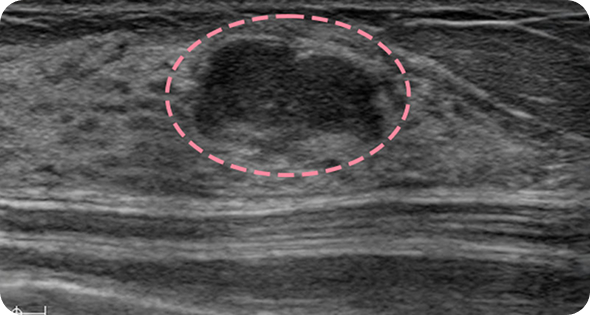

유방 섬유선종은 20~30대 젊은 여성에게 흔히 발생하는 양성 종양 으로, 대체로 위험성이 크지 않습니다. 하지만 드물게 악성으로 진행하는 경우가 있고 환자분께서 가족력으로 인한 불안을 느끼셔서 이번 사례에서는 예방적 차원에서 제거를 시행했습니다. 수술은 어렵지 않게 진행되었고, 1년 후 검사에서도 반흔 외에 재발 없이 깨끗한 결과를 확인할 수 있었습니다.